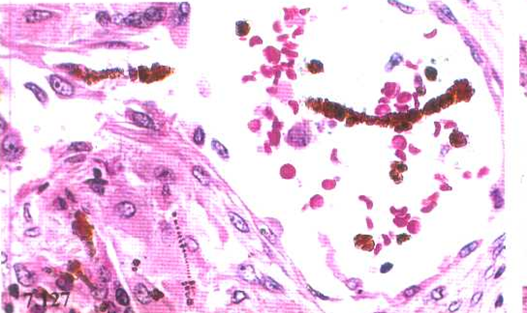

石棉小体(asbestos body) 系石棉纤维被巨噬细胞吞噬后,由一层含铁蛋白颗粒和酸性黏多糖包裹沉积于石棉纤维之上所形成。肺组织切片中可见长10~300μm,粗1~5μm的石棉小体,呈黄色或黄褐色,形似哑铃、鼓槌或串珠状,普鲁氏蓝染色时常呈阳性铁反应。石棉小体仅仅是吸入石棉的标志,其数量的多少与肺纤维化程度不一定平行。

石棉小体(asbestos body) 石棉小体(asbestos body)